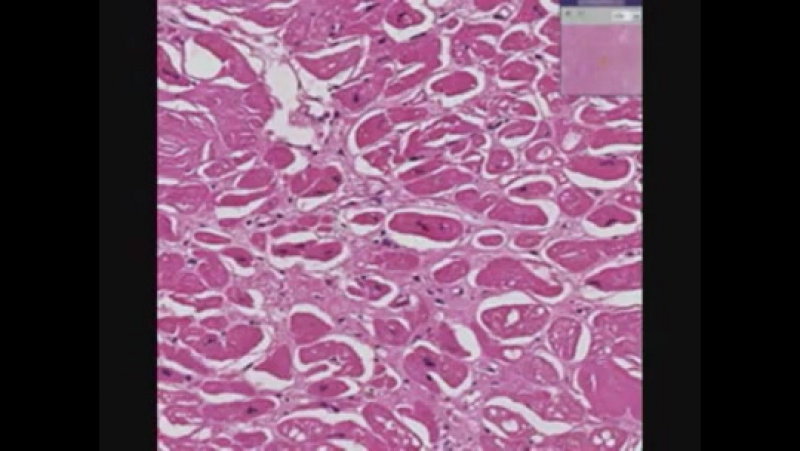

Амилоидоз миокарда

Амилоидоз миокарда 109 фото